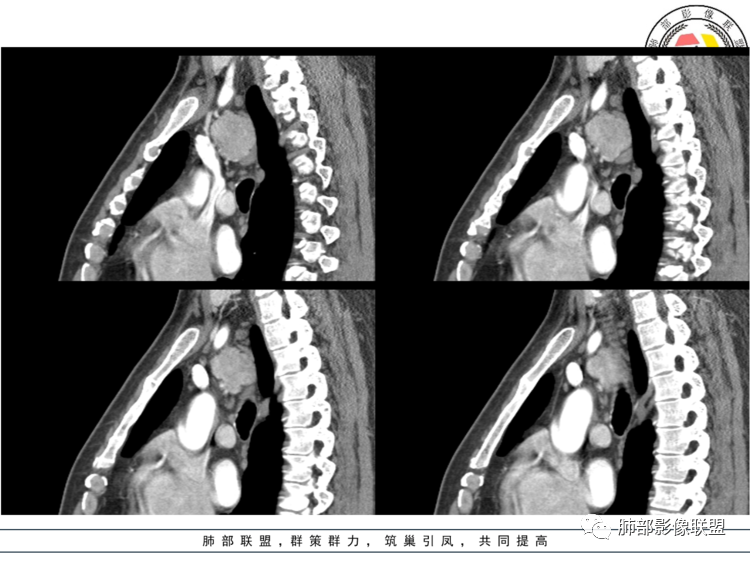

3.1单发型CD的肺部表现

单发型CD多为透明血管型,所以明显强化和中央分枝状钙化具有特征性。在CT上表现圆形或类圆形软组织密度影,伴或不伴周围淋巴结增生,体积一般较大,边缘光整,病灶中央的弧形、线样、分枝样及枯枝样钙化(因为肿块内增生的血管组织玻璃样变或退变后钙盐沉积,故多呈血管样铸型的分支状或枯枝状);透明血管型因为其内血供丰富,周围可见粗大的供血动脉,在多期扫描动脉早期明显强化,强化程度与大血管相仿,又由于病灶内血管壁玻璃样变或纤维化及内皮细胞过度增生致血管腔狭窄,对比剂退出减慢,故延迟扫描扫描仍可持续强化,呈“早进晚出”的强化方式。因为其血供丰富,坏死、囊变或出血少见,但是有时候病灶内灶状或条片状低密度影,是纤维组织或发生玻璃样变性的血管结构,而不是缺血坏死区。